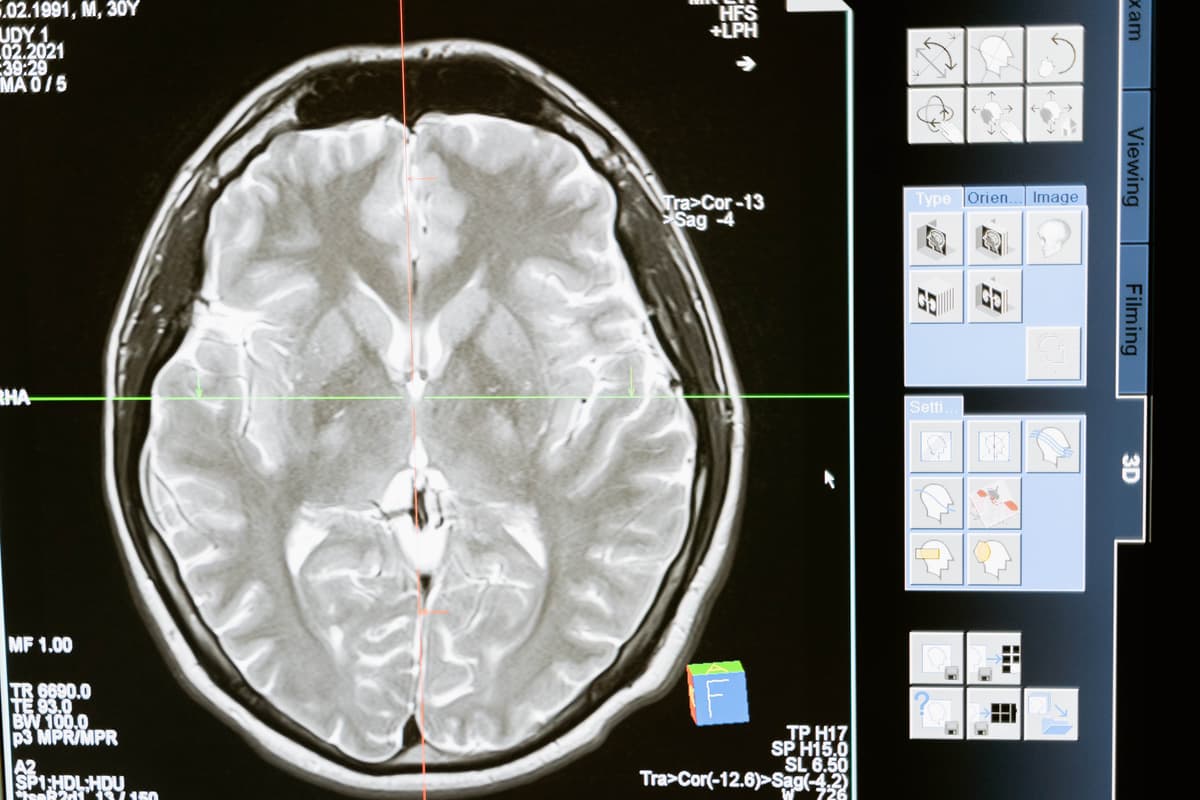

Accurate diagnosis of a brain aneurysm is crucial for determining the appropriate treatment plan. Diagnostic methods include medical imaging techniques such as magnetic resonance imaging (MRI) and computed tomography angiography (CTA), which enable healthcare professionals to visualize the blood vessels in the brain and identify any potential aneurysms.

Timely treatment is of utmost importance in managing brain aneurysms. Once diagnosed, healthcare providers may recommend either surgical intervention or endovascular coiling, depending on the size, location, and risk factors associated with the aneurysm. Prompt treatment can significantly reduce the risk of rupture and subsequent complications.

Despite the widespread availability of brain imaging that can detect a ruptured brain aneurysm, misdiagnosis or delays in diagnosis occur in up to one quarter of patients when initially seeking medical attention. Worryingly, in three out of four cases, misdiagnosis results from a failure to do a scan.